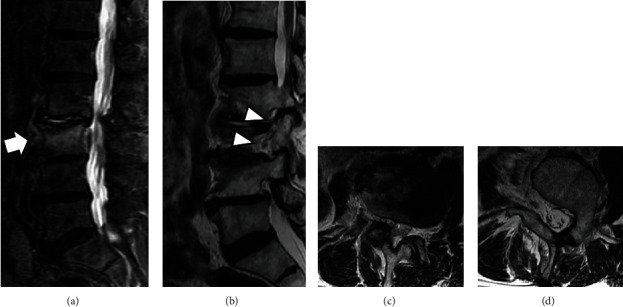

Background: Patients with congenital absence of a lumbar pedicle and nerve root anomaly presenting with ipsilateral foraminal stenosis are extremely rare. Case Presentation: An 80-year-old man had low back and right thigh pain. Radiographs and computed tomography (CT) showed L3 vertebral body fracture and the absence of the right L3 lumbar pedicle. He was diagnosed with L2-L3 right foraminal stenosis caused by an L3 vertebral fracture and underwent lumbar fusion at L2-L3 and L3-L4. Intraoperatively, we confirmed that an anomalous nerve root was divided from the right L2 nerve root near the dorsal root ganglion (DRG). Conclusions: Patients with congenital absence of a lumbar pedicle are less prone to ipsilateral foraminal stenosis because they theoretically have a large space in the foramen. This rare case was caused because of additional instability due to vertebral fracture under the condition of a nerve root anomaly and lumbar degeneration.